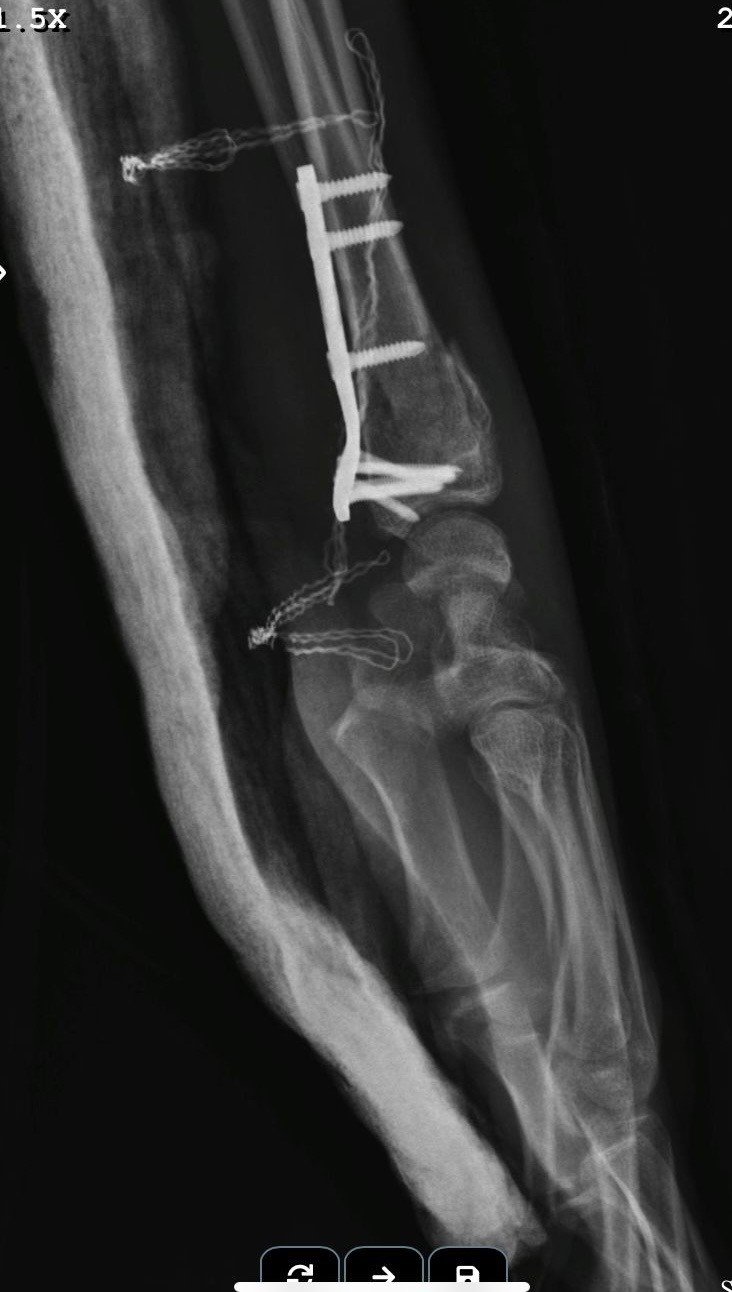

"Beş gün entübe edildi. Ne olacağı belli değildi çıkmama ihtimali vardı. Şükürler olsun doktorlarımız ve Rabbim sayesinde entübeden çıktık. Hatta ciğerin birisinde infilak vardı; ciğer sorunumuzdan dolayı özellikle yoğun bakımda entübediydik. Beş günün sonunda ciğerleri toparlamaya başladı; entübeden çıkarttılar. Solunumu normale döndü. Sırayla sağlığı yerine gelmeye başladı. Bir hafta sonra kolundan ameliyat oldu platin koydular. Omurilikten ameliyat olduk. Omuriliğinde ilk röntgende tek kırık gördüler; üç kemiği birbirine bağlayacaklardı. Sonradan ikinci röntgende üç kırık olduğunu gördük; yedi kemiği birbirine bağladılar. Omuriliğe platin takıldı. 14 tane civatamız var. Şükürler olsun doktorlarımıza, Allah razı olsun. Evladımız gayet iyi, sağlıklı, yerinde. Artık işte suratta, çenede, burunda, elmacık kemiklerinde parçalı kırıklarımız var. Osman Gazi Fakültesi'nde Allah'ın izniyle buradaki hocalarımıza, önce Rabbim'e sonra hocalarımıza emanet çocuğumuz. İnşallah daha iyi olacağız; ben kendi adıma söylüyorum. Çocuğuma, her motora bindiklerinde sürekli kask ve montlarını giymelerini tembihliyordum. Giymediklerinde fırça atıyordum. Eskişehir'de birçok yerde tanınırız, tanırlar. Sevenimiz, eşimiz, dostumuz çok; uyarırlar, telefon gelir, haber verirler. Her duyduğumda, gördüğümde söylerim. Sağ olsun, çocuğum da o gün beni dinlemiş, kaskını takmış. Şükürler olsun ki takmış; takmasaydı o gün, o kazada belki çocuğumuzu kaybederdik."